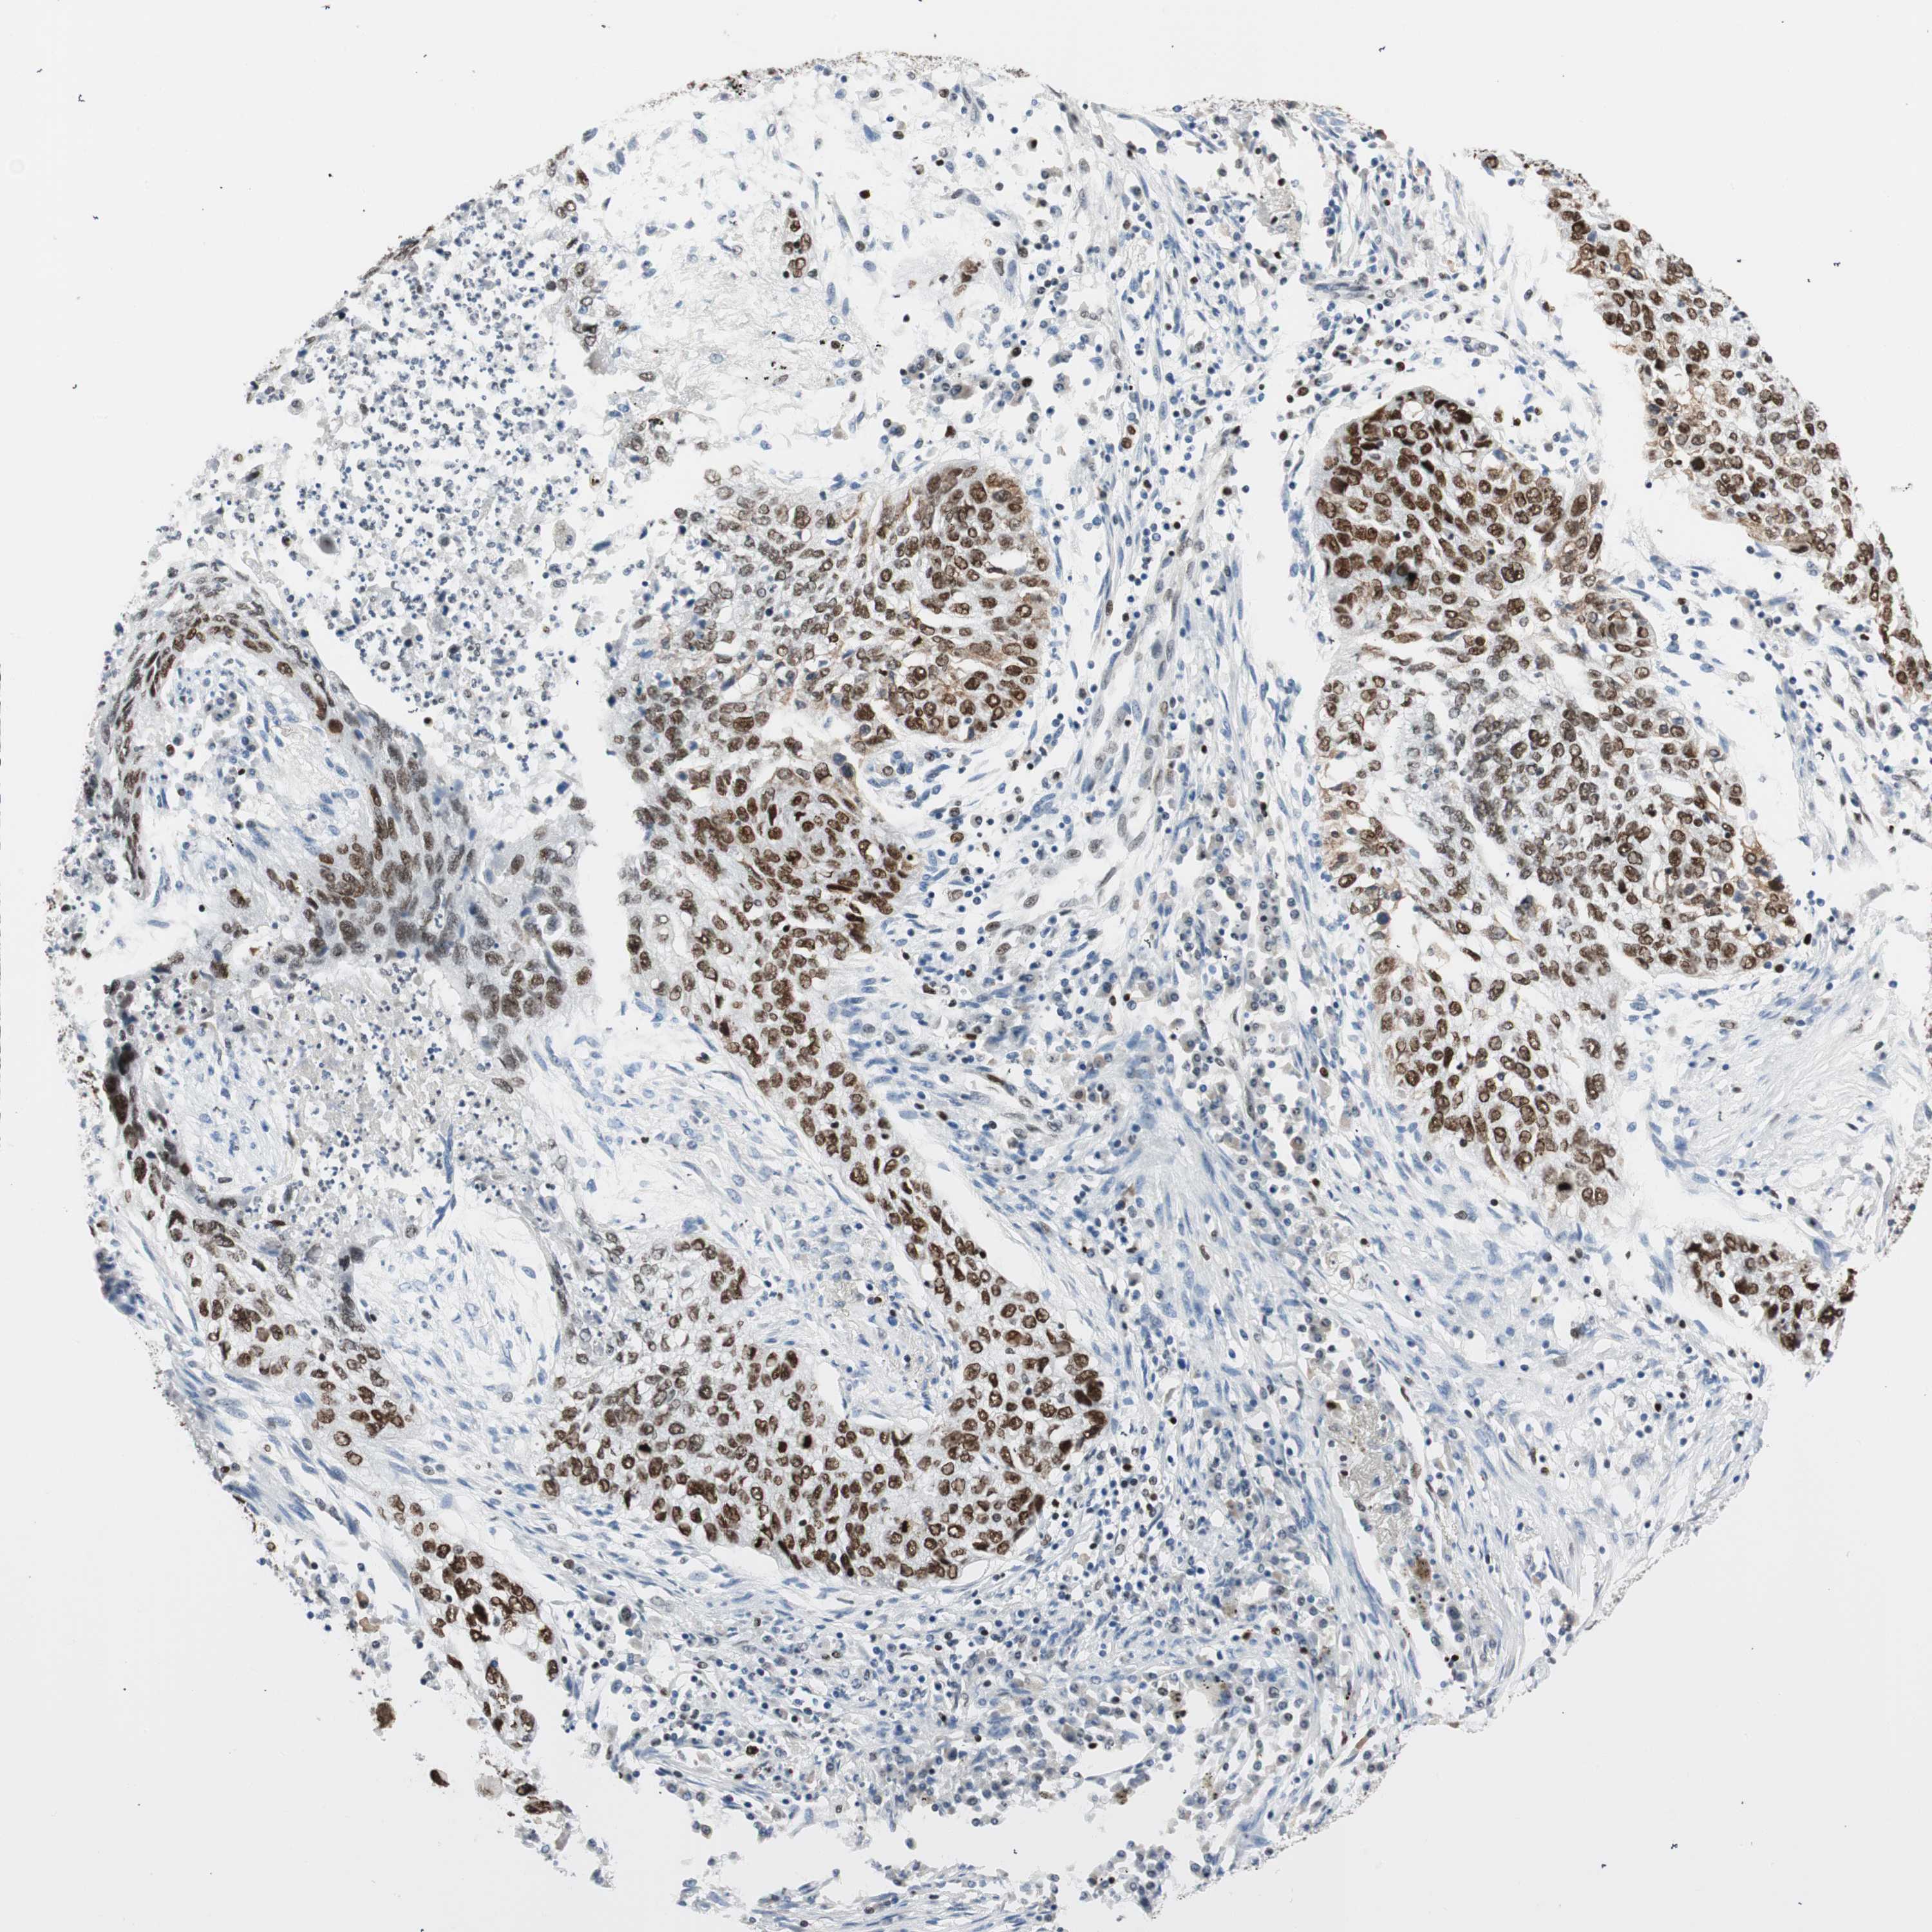

CANCER LUNG CANCER Show tissue menu

EZH2 is not prognostic in Lung Adenocarcinoma (validation)

EZH2 is not prognostic in Lung Squamous Cell Carcinoma (TCGA)